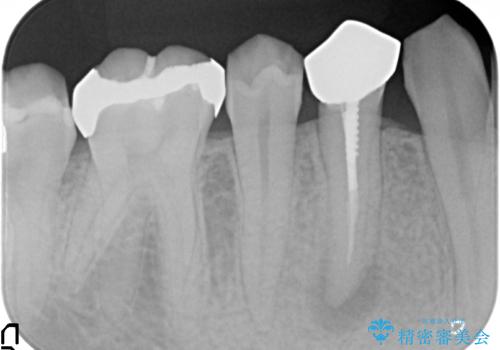

- 右下4番目の歯でものを咬むと疼くような痛みがあるといらっしゃった方の症例です。

X線上で根尖病変を認めたため再根管治療を行い、症状改善後、オールセラミッククラウンによる補綴を行いました。